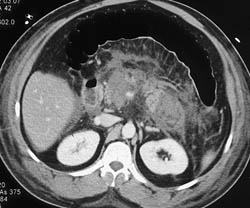

Pancreatic Cancer Encases the Celiac and SMA